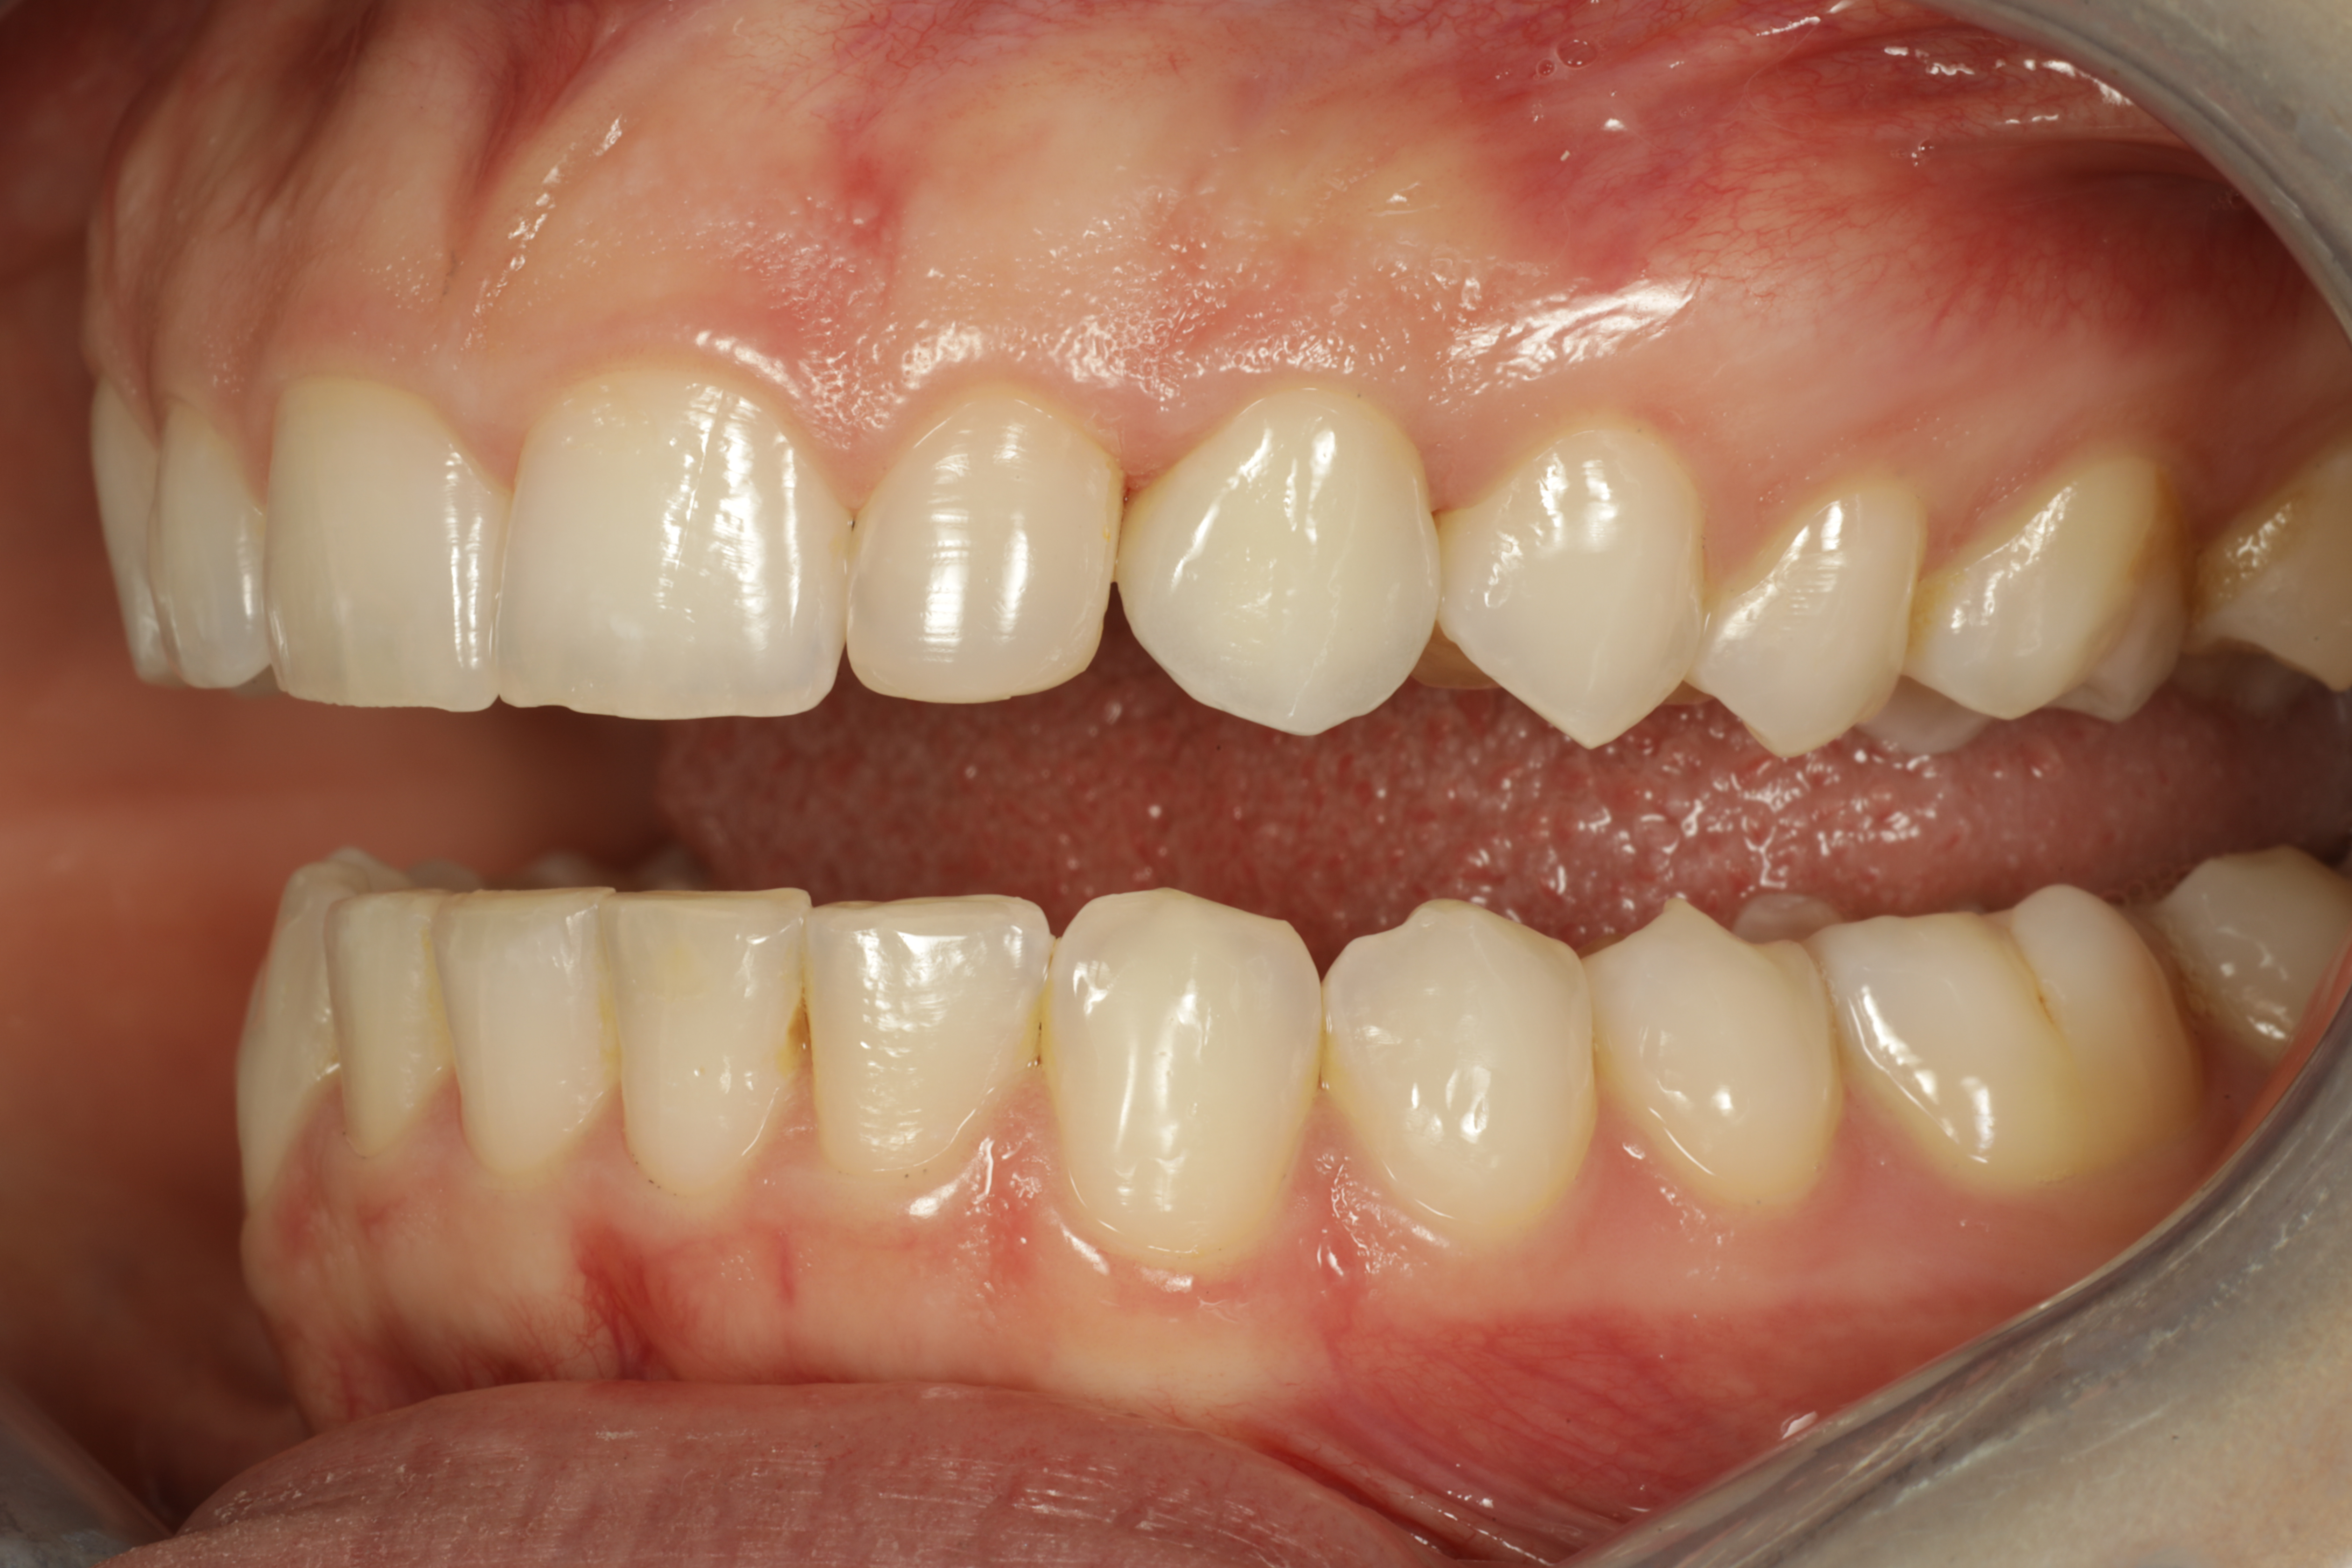

Alkunäkymä huulet retraktoreilla sivuun loitonnettuina.

Esimerkkitapauksena nuori 25-vuotias nainen, jolla puuttuivat syntymästä pysyvät reunimmaiset yläetuhampaat eli inkisiivit. Pysyvät kulmahampaat ovat siirtyneet niiden paikalle sekä maitokulmahampaat ovat vielä paikoillaan. Hoidosta oli esteettisesti haastava toteuttaa, koska yläetuhampaiden ienrajat tulisivat olla samalla tasolla (2).